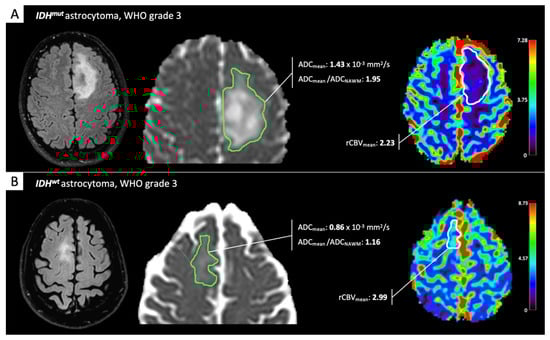

- Lee, M.K.; Park, J.E.; Jo, Y.; Park, S.Y.; Kim, S.J.; Kim, H.S. Advanced imaging parameters improve the prediction of diffuse lower-grade gliomas subtype, IDH mutant with no 1p19q codeletion: Added value to the T2/FLAIR mismatch sign. Eur. Radiol. 2020, 30, 844–854. [Google Scholar] [CrossRef] [PubMed]

- Xing, Z.; Yang, X.; She, D.; Lin, Y.; Zhang, Y.; Cao, D. Noninvasive assessment of IDH mutational status in World Health Organization grade II and III astrocytomas using DWI and DSC-PWI combined with conventional MR imaging. Am. J. Neuroradiol. 2017, 38, 1138–1144. [Google Scholar] [CrossRef]